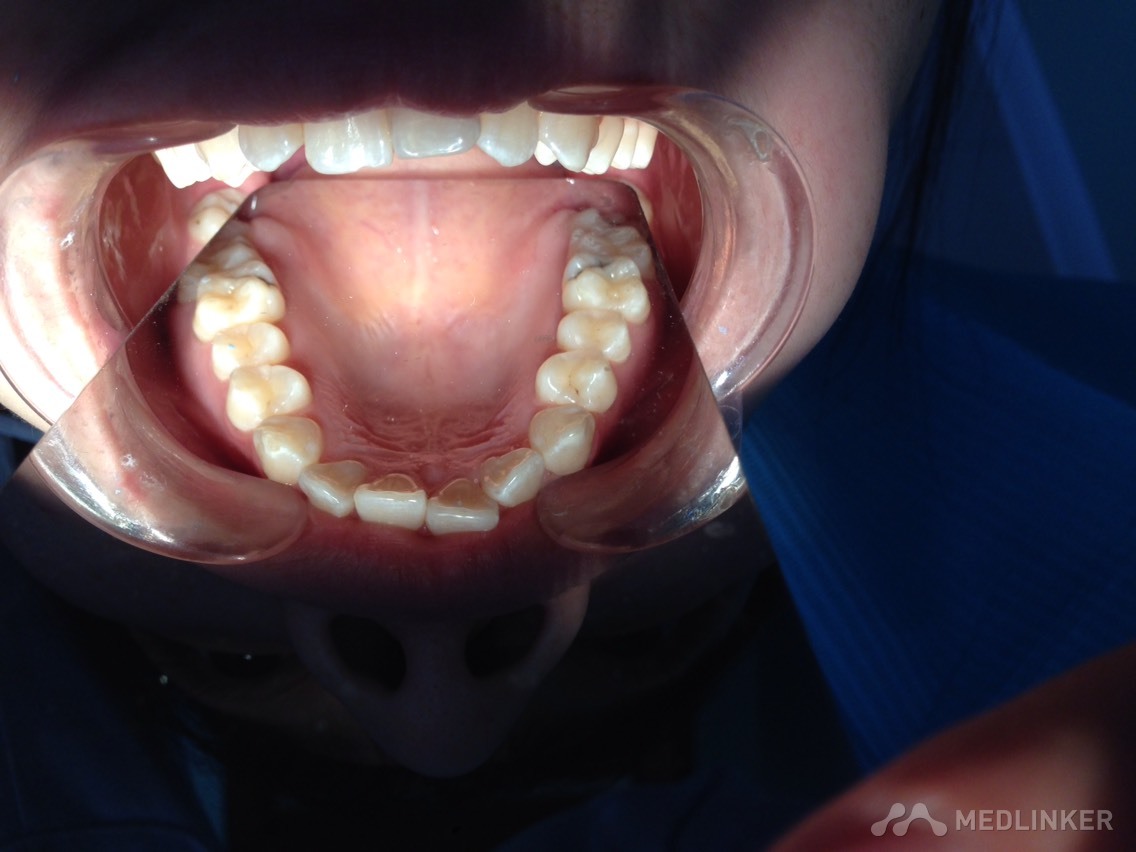

患者女,23岁,想做隐形无托槽矫正

上颌前牙牙列拥挤,下颌前牙散在间隙,下颌双侧第一磨牙缺失多年,开合